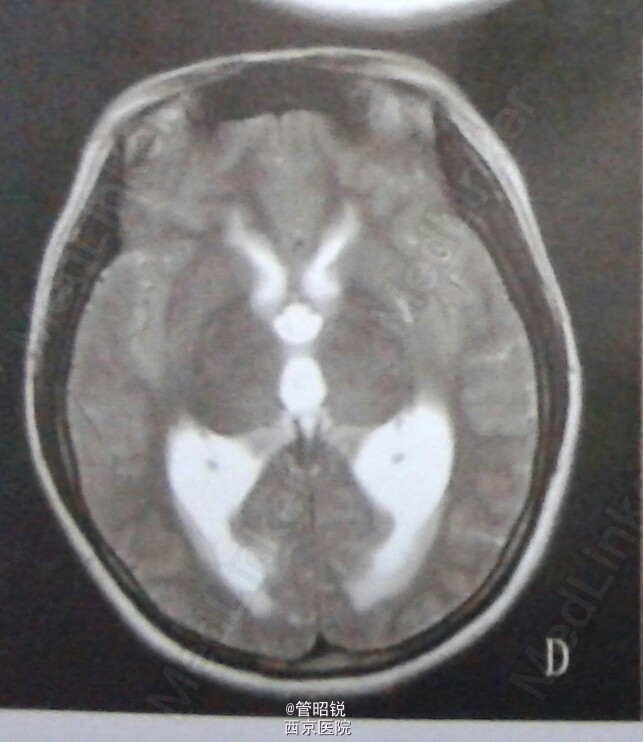

主诉:头痛伴恶心呕吐10余天 现病史:患者,女,23岁,主因"头痛伴恶心呕吐10余天“于2013年11月6日入院,患者10天前无明显诱因出现头痛,为全头胀痛,枕部明显,伴恶心呕吐,呕吐物为胃内容,无发热,自觉周身乏力,于外院就诊。具体治疗不详,上述症状无好转,头痛逐渐加重,自发病来无意识障碍,吞咽困难等症状 既往史:癫痫病史10余年,自服药物不详,控制欠佳。 入院体检:T:36.6摄氏度,R;82次/分 血压128/95mmHg,神志清,言语正常,眼部检查除外展略欠佳外,余未见异常。颈强及Kerning征阳性,四肢肌力四级。肌张力正常。膝反射亢进,双侧巴氏征阳性。眼底示双眼视乳头水肿,余查体未见异常。影像学检查如下图 辅助检查:卡马西平、丙戊酸、苯妥英钠血药浓度0.00ug/ml 诊断为:急性小脑炎 治疗:脱水降颅压及营养神经治疗